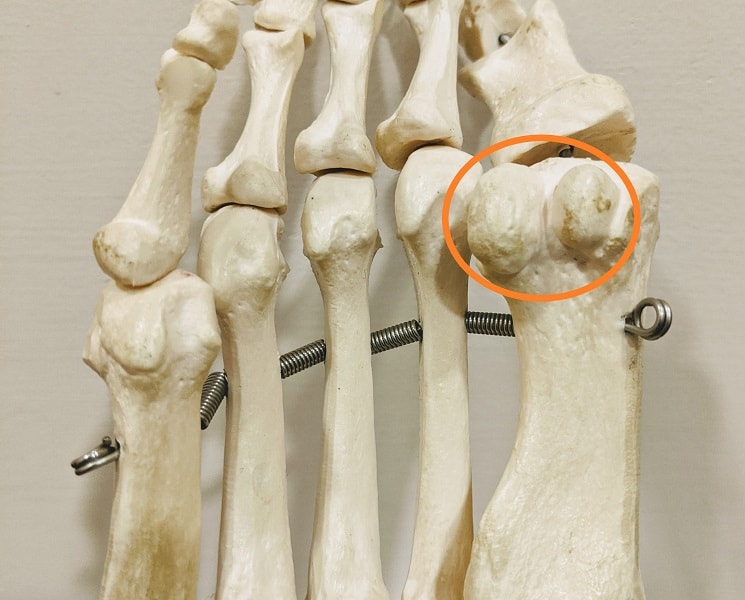

Анатомия: Блоки и сесамовидные кости в деталях